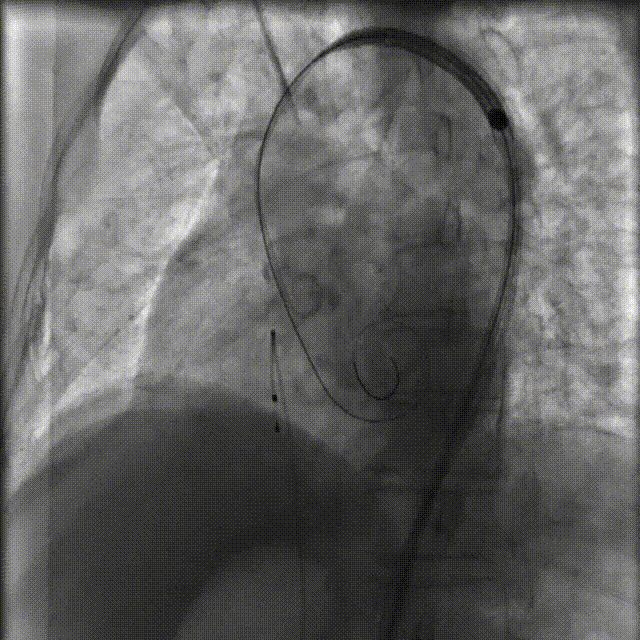

瓣膜输送系统于LAO view通过主动脉弓(Flush port朝向3点钟方向以确保commissure alignment)

图片

过弓